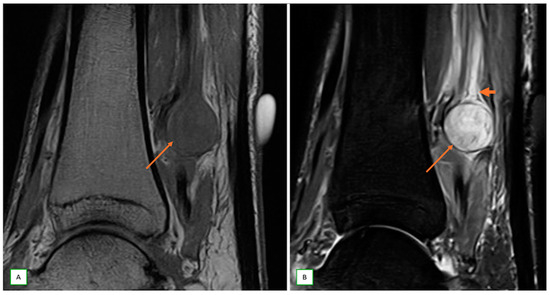

- Intraneural ganglion cysts usually occur near joints; are particularly common in the common peroneal nerve at the knee, owing to the intraarticular branch of the proximal tibiofibular joint; and appear as tubular, multiloculated cystic lesions following the course of the nerve on MRI [60,61] (Figure 16).